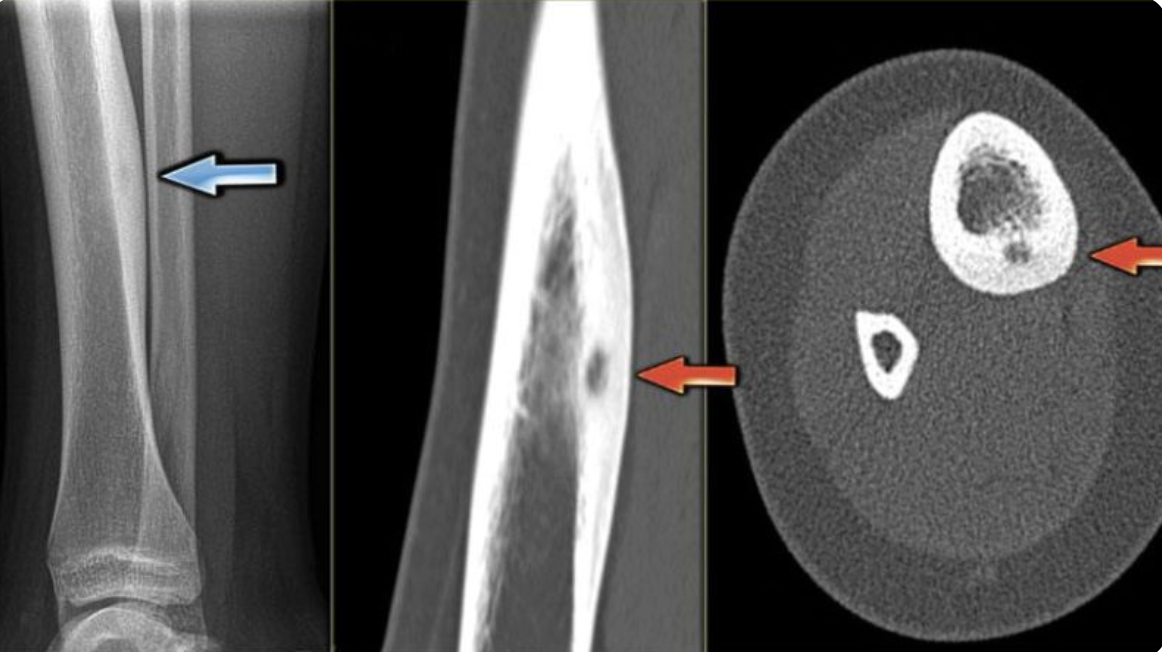

Tôi bị chòi xương (osteoma) và dự định phẫu thuật tại Bệnh viện Đại học Y Dược TPHCM. Tôi có thẻ BHYT nhưng đăng ký khám chữa bệnh ban đầu ở Cà Mau.